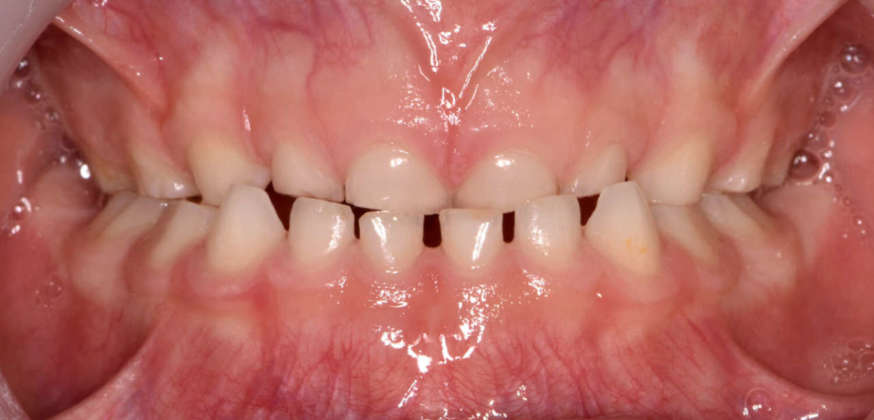

I soggetti risultati positivi alla poligrafia vengono poi indirizzati alla raccolta della documentazione fotografica per uno studio più dettagliato delle caratteristiche extraorali e intraorali (Figura 2).

Tale studio permette di approfondire determinati aspetti morfologici predisponenti alle OSAS, come particolari caratteristiche occlusali e craniofacciali12, ipertrofia adenotonsillare, anchiloglossia, deglutizione atipica ecc. Per un completo studio del caso viene richiesta, infine, l’esecuzione delle seguenti radiografie: l’ortopantomografia, la teleradiografia in proiezione latero-laterale e, in particolari situazioni cliniche, la CBCT per uno studio più approfondito delle vie aeree superiori (Figura 3).